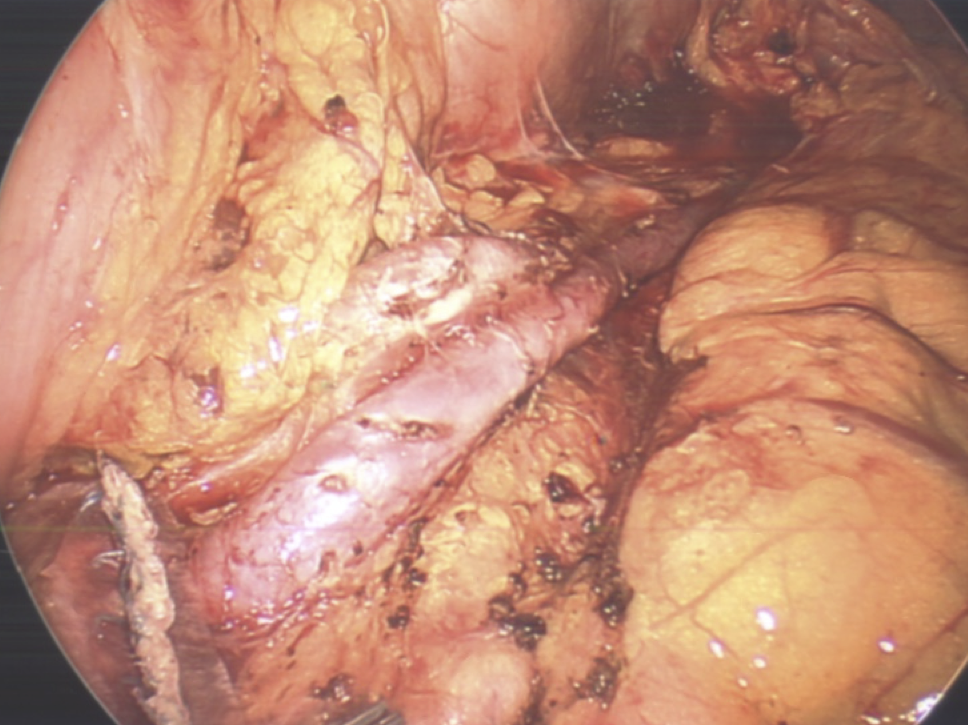

With many years experience as a liver transplant surgeon, Dr. de la Torre was the first to perform a major liver resection laparoscopically in the state of New Jersey, and has been performing laparoscopic liver surgery since 2007. Dr. de la Torre has 25 years of experience in surgery of the liver, pancreas, bile ducts, management of cirrhosis, portal hypertension, and liver cancer. Dr. De la Torre specializes in tissue sparing laparoscopic liver surgery in patients with cirrhosis, allowing the possibility of avoiding liver transplant for tumors located in the liver that were once deemed not feasible to remove. Dr. de la Torre published "A Sling Technique For Laparoscopic Resection of Segment Seven of the Liver" in the Journal of the Society of Laparoendoscopic Surgery 2018 Apr-Jun; 22(2) and most recently "Sling Technique for Laparoscopic Liver Mobilization" Journal of the Society of Laparoscopic and Robotic Surgeons 2024 Apr-Jun;28(2). While most other surgeons in New Jersey start laparoscopically and eventually open, 95% of our patients start laparoscopically and end laparoscopically without compromise in surgical quality or safety.

In addition to laparoscopic liver surgery, Dr de la Torre specializes in laparoscopic pancreas surgery, performing the Whipple Procedure through a 3-4 inch incision. The pancreas leak rate has been 0%. Patients have less pain, shorter hospital stay (4-7 days) and even a lower hospital bill.